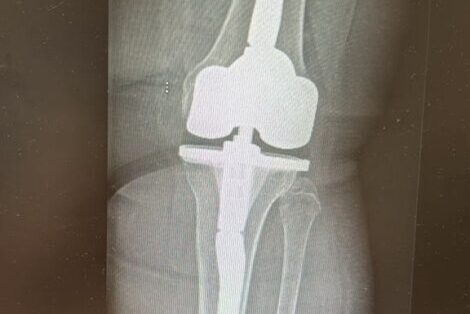

В чем преимущества эндопротезирования коленного сустава по ОМС и квоте?

Эндопротезирование коленного сустава — это высокотехнологичная операция, способная кардинально улучшить качество жизни пациентов с тяжелыми поражениями колена. Когда консервативные методы лечения исчерпаны, а боль и ограничение подвижности становятся постоянными спутниками, замена сустава часто становится единственным выходом. В России граждане могут пройти эту дорогостоящую процедуру в рамках программы обязательного медицинского страхования (ОМС) и системы квотирования высокотехнологичной медицинской помощи (ВМП).

Использование качественных современных имплантатов

Клиники, работающие в системе ОМС и ВМП, обязаны использовать только сертифицированные эндопротезы, соответствующие строгим российским и международным стандартам качества и безопасности. Хотя пациент не выбирает конкретную модель протеза самостоятельно (она определяется медицинскими показаниями и протоколами клиники), он может быть уверен, что имплантат обладает необходимыми характеристиками долговечности и функциональности. Производители эндопротезов для государственных программ проходят тщательный отбор.